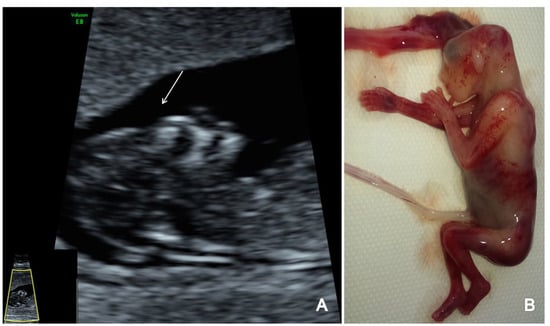

Figure 1.

The FTAS protocol for CNS evaluation: (A) transverse view of the brain showing the contour and shape of the fetal skull, choroid plexus (arrow) and the filling of lateral cerebral ventricles (arrow); (B,C) further evaluation of the cerebral ventricular system, in transverse planes of the brain showing the third ventricle (B) and aqueduct of Sylvius (C) (arrow); (D) mid-sagittal view of the brain showing the thalamus (Tha) and the measurements for the brain stem (BS), the fourth ventricle (IT), cisterna magna (CM), the nuchal translucency (NT) and the brain stem–occipital bone ratio (BSOB); (E) longitudinal view of the spine regularity and underlying skin (arrow).

All three cases of anencephaly were easily identified due to absence of the skull ossification and the clear deformity of the brain with no visualization of the normal CNS US features (Figure 6). The spine with the overlying skin was found unaffected.

Figure 6.

A case of anencephaly diagnosed at 12 weeks + 4 days weeks (Case7): (A) sagittal view of the absence of cranial bones ossification (arrow); (B) specimen presentation aspect after medical TOP.